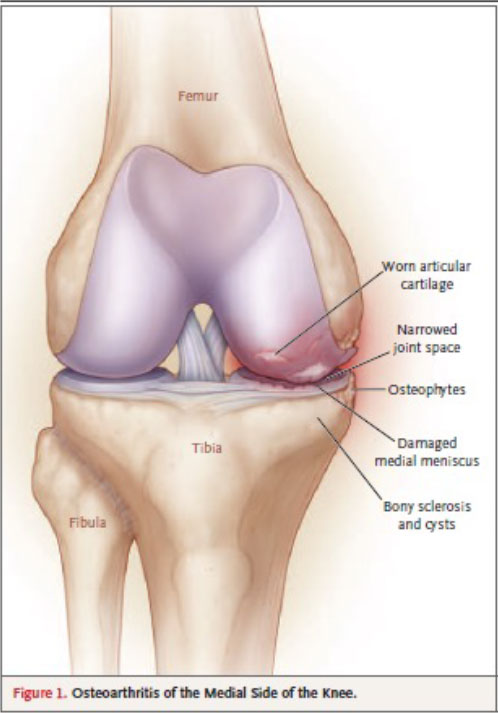

Osteoarthritis (OA) is known as the most common chronic disease of the cartilage. As the cartilage breaks down due to wear-and-tear and/or mechanical stress, it causes swelling, pain and inflammation, leading to extracellular matrix (ECM) loss¹ .- Knee osteoarthritis (KOA) is a progressive joint disease that often involves intra- and per articular structures² and is considered pathology characterized by articular cartilage lesions, synovitis, subchondral sclerosis, and osteophytes³.

inflammation⁴. Knee OA commonly results in knee pain and decreases patients’ mobility (e.g. walking and stair climbing)⁵. - The pain of osteoarthritis is usually related to activity. For osteoarthritis of the knee (Fig. 1), activities such as climbing stairs, getting out of a chair, and walking long distances bring on pain.